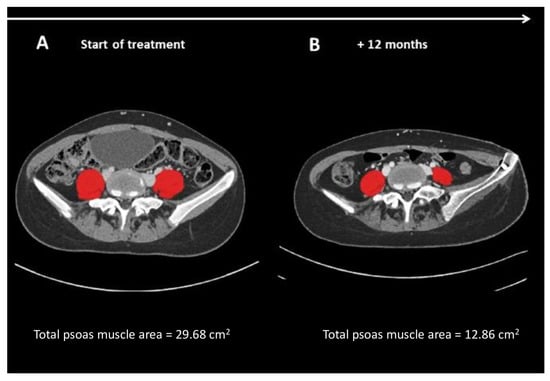

- To describe the clinical characteristics, nutritional status (defined by the BMI and the PNI), and the presence of sarcopenia (defined by the measurement of tPMA detected by axial CT images of the L4–L5 vertebrae) at diagnosis and after 12 months of chemotherapy in pediatric patients with bone and soft tissue sarcomas.

| tPMA L4–L5 (mm2) | 13.2 (8.8; 19.4) | 11.5 (9.95; 18.48) | 0.31 |

| tPMA L4–L5 Z-score | −1.01 (−1.71; −0.35) | −1.46 (−2.57; −1.11) | 0.005 |